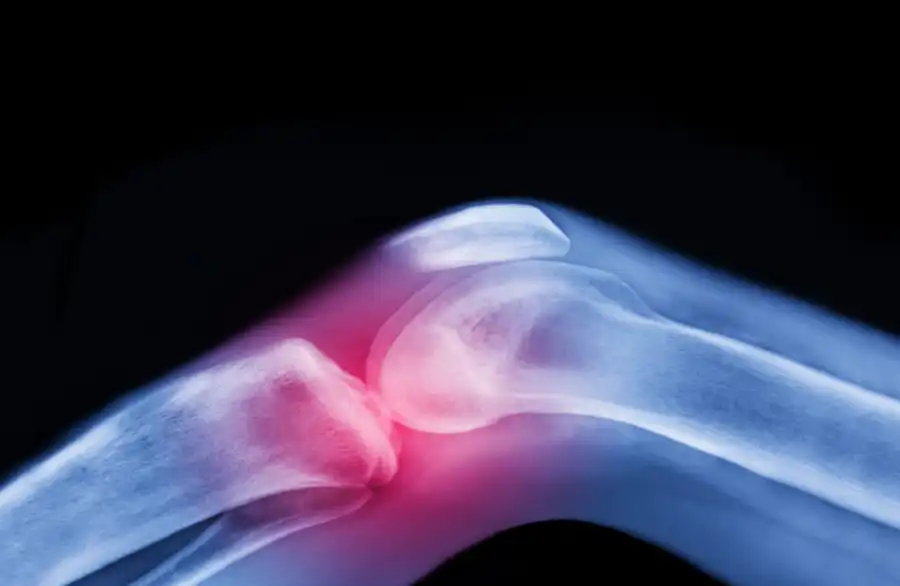

مدار الساعة - ابتكر علماء طريقة جديدة لعلاج التهاب المفاصل التنكسي (الفصال العظمي) عبر زراعة ركبة بشرية حية في المختبر، في خطوة قد تغير حياة الملايين من المرضى.

ويهدف هذا الإنجاز إلى استعادة وظيفة المفصل الطبيعية وتخفيف الألم الذي يعيق الحركة اليومية.وفي جامعة كولومبيا، صنع العلماء هيكلا ثلاثي الأبعاد للركبة من مواد قابلة للتحلل الحيوي، ثم أضافوا إليه خلايا العظام والغضاريف. وعلى مدار نحو عام، تجدد الغضروف وأنسجة العظام، بينما تحلل الهيكل تدريجيا، لتنتج ركبة كاملة جاهزة للزراعة.ويأمل العلماء أن يكون هذا المفصل الجديد قابلا للزرع في المرضى، ليشكل حلا دائما لهذه الحالة المؤلمة.

وحتى الآن، اختبر العلماء النماذج الأولية في جثث لاختبار قدرتها على تحمل الوزن والمشي، ويخططون لزراعتها لدى حيوانات كبيرة قبل التجارب البشرية. ويمكن استخدام خلايا جذعية مأخوذة من المريض نفسه أو من متبرع، لضمان نجاح الزراعة. وعند زرع الركبة الحية، تتصل بالأوعية الدموية للجسم لتعمل تماما كالركبة الأصلية.ولا يقتصر الابتكار في هذا المجال على الركبة فقط. ففي جامعة Duke، طور العلماء حقنة تحفز نمو الغضروف والعظام المفقودة داخل المفصل، وفرت راحة طويلة الأمد في تجارب على الحيوانات، ما يمهد الطريق لتجارب بشرية مستقبلية.وفي جامعة كولورادو بولدر، ابتكر فريق بحثي حقنة واحدة قادرة على تحفيز الجسم لإصلاح الغضروف التالف خلال أسابيع، مع إمكانية إصلاح كامل للعيوب في العظم والغضروف. ومن المتوقع أن تبدأ التجارب السريرية على البشر خلال 18 شهرا تقريبا.وتأتي هذه الإنجازات بدعم من وكالة مشاريع الأبحاث المتقدمة للصحة (ARPA-H) ضمن برنامج "NITRO"، الذي يهدف إلى تطوير علاجات تحفز المفاصل على الشفاء الذاتي، لتخفيف الألم أو القضاء عليه، وتقليل الحاجة لعمليات استبدال المفاصل الجراحية. يعد التهاب المفاصل التنكسي (الفصال العظمي) أكثر أنواع التهاب المفاصل شيوعا، مع زيادة عدد المصابين عالميا بنسبة 132% منذ عام 1990. ويشير الأطباء إلى أن الشيخوخة والسمنة، بالإضافة إلى عوامل اجتماعية واقتصادية، تجعل بعض الفئات أكثر عرضة للإصابة. ومع هذا التقدم العلمي، من المتوقع أن يحصل المزيد من المرضى قريبا على خيارات علاجية مبتكرة تحسن جودة حياتهم.